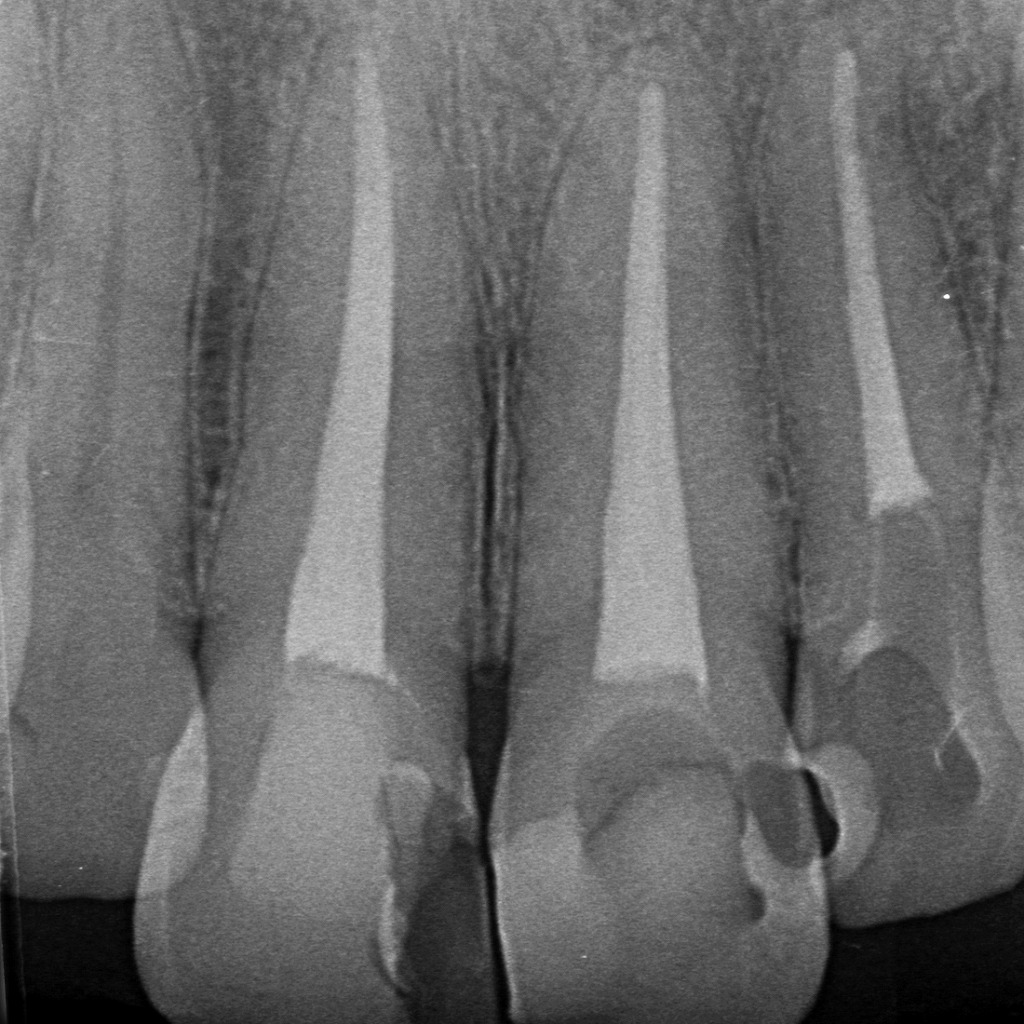

下顎大臼歯の根充後X線写真を例に

下顎の大臼歯は、歯の中でも最も根管治療が難しい部位といわれます。その理由は、根管の構造が非常に複雑で、器具操作が難しいためです。下記のポイントが、治療が長期化する主な要因となります。

1. 根管が大きく湾曲している

下顎大臼歯の遠心根・近心根は、しばしば大きくカーブしています。

添付のレントゲン写真でも、根尖付近で根管が大きく弯曲している様子が確認できます(赤矢印部分)。

この湾曲があることで

- 器具が根の形に沿って進みにくい

- 器具が破折するリスクが上がる

- 洗浄・拡大が不十分になりやすい

といった問題が生じ、治療時間がどうしても長くなります。

2. 根管が非常に細く、内部構造が複雑

大臼歯には通常、3〜4本の根管がありますが、それぞれが細く、分岐(支根管)も多く存在します。

特に下顎大臼歯の近心根は、

- 2つの根管が内部でつながっている(イスムス)

- 途中で枝分かれする(側枝)

など複雑な形態を示すことが多く、清掃が困難です。

③ 垂直加圧充填(垂直根充)

ガッタパーチャを加圧して側枝の方向にまで緊密に封鎖できるため、

側枝感染の再発防止に有効です。

ガッタパーチャを垂直方向に加圧して柔らかくし、主根管だけでなく側枝の先端まで緊密に封鎖する“垂直加圧充填”の症例。赤矢印は側枝方向まで充填材が行き渡っている状態を示しています。複雑な側枝形態でも細菌の侵入を防ぎ、治療後の再感染リスクを大幅に下げることができます。